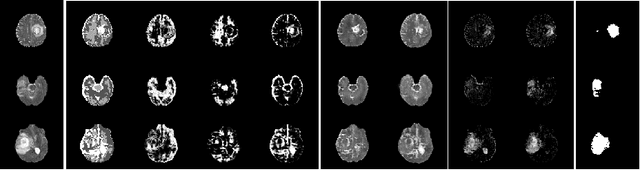

The goal of unsupervised anomaly segmentation (UAS) is to detect the pixel-level anomalies unseen during training. It is a promising field in the medical imaging community, e.g, we can use the model trained with only healthy data to segment the lesions of rare diseases. Existing methods are mainly based on Information Bottleneck, whose underlying principle is modeling the distribution of normal anatomy via learning to compress and recover the healthy data with a low-dimensional manifold, and then detecting lesions as the outlier from this learned distribution. However, this dimensionality reduction inevitably damages the localization information, which is especially essential for pixel-level anomaly detection. In this paper, to alleviate this issue, we introduce the semantic space of healthy anatomy in the process of modeling healthy-data distribution. More precisely, we view the couple of segmentation and synthesis as a special Autoencoder, and propose a novel cycle translation framework with a journey of 'image->semantic->image'. Experimental results on the BraTS and ISLES databases show that the proposed approach achieves significantly superior performance compared to several prior methods and segments the anomalies more accurately.